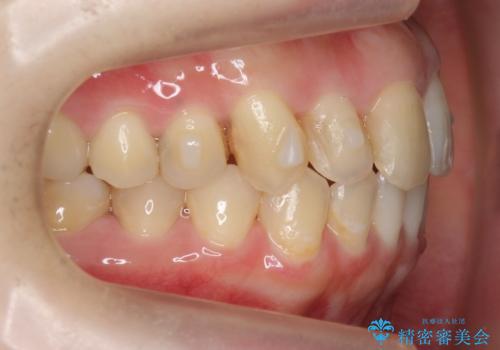

犬歯のねじれ 上の歯が引っ込んでいる

- 前歯の並びを気にして来院。

インビザラインで、上の前歯をやすり掛けして並べました。